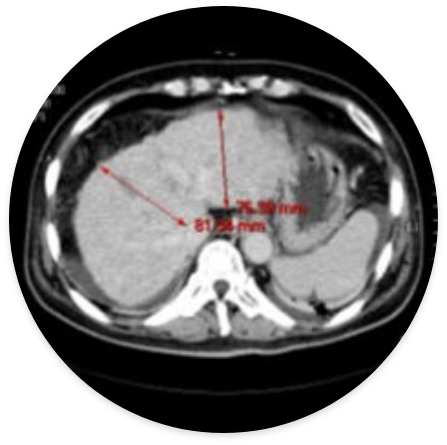

간경변 (59세 남성) – 시술 후 간세포가 재생되어 간의 크기가 증가하고 간 조직이 부드러워짐